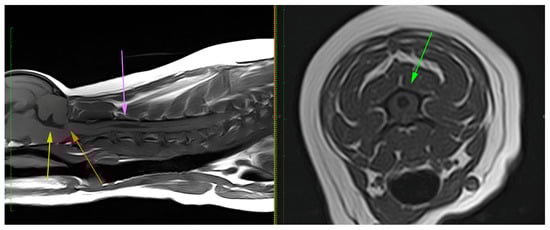

There was no statistically significant difference for breed and sex (p = 0.32) or breed and age (p = 0.318), meaning that sex and age were comparable for all breeds. However, there was a statistically significant difference for all breeds for CM (p < 0.001), SM (p = 0.003) and syrinx size (p = 0.003), meaning that CM1/CM2 and SM+ were present at a significantly higher rate in all breeds. CM was seen the most in the Chihuahua (75%), Griffon (96%), Maltese (83%), Pug (75%) and Yorkshire terrier (80%) breeds. CM and/or SM were only seen in one out of nine Dachshunds. SM was observed in all breeds, with the highest frequency in the Griffon (89%), French Bulldog (70%) and Chihuahua (62%). Only in the French Bulldog was there evidence of a high number of dogs being affected by SM and not CM. In all other breeds, CM and SM appeared to predominantly occur simultaneously (Table 2). In all breeds, SM was observed with an average syrinx size of 2.9 ± 2.4 mm (Mean ± SD), with the French Bulldog, Pug, Griffon and Chihuahua having larger syrinxes (Table 2). MEE was only seen in the French Bulldog, two Chihuahuas and four crosses. Figure 1 and Figure 2 are examples of two of the collected MRI images.

Figure 1.

Example of a T1-weighted MRI of an 8-year-old Chihuahua. Yellow arrow—dilatation of the 4th ventricle; orange arrow—Chiari-like malformation; purple and green arrow—a large syrinx with a diameter of 3.1 mm. Taken with a 1.5 T MRI scanner.